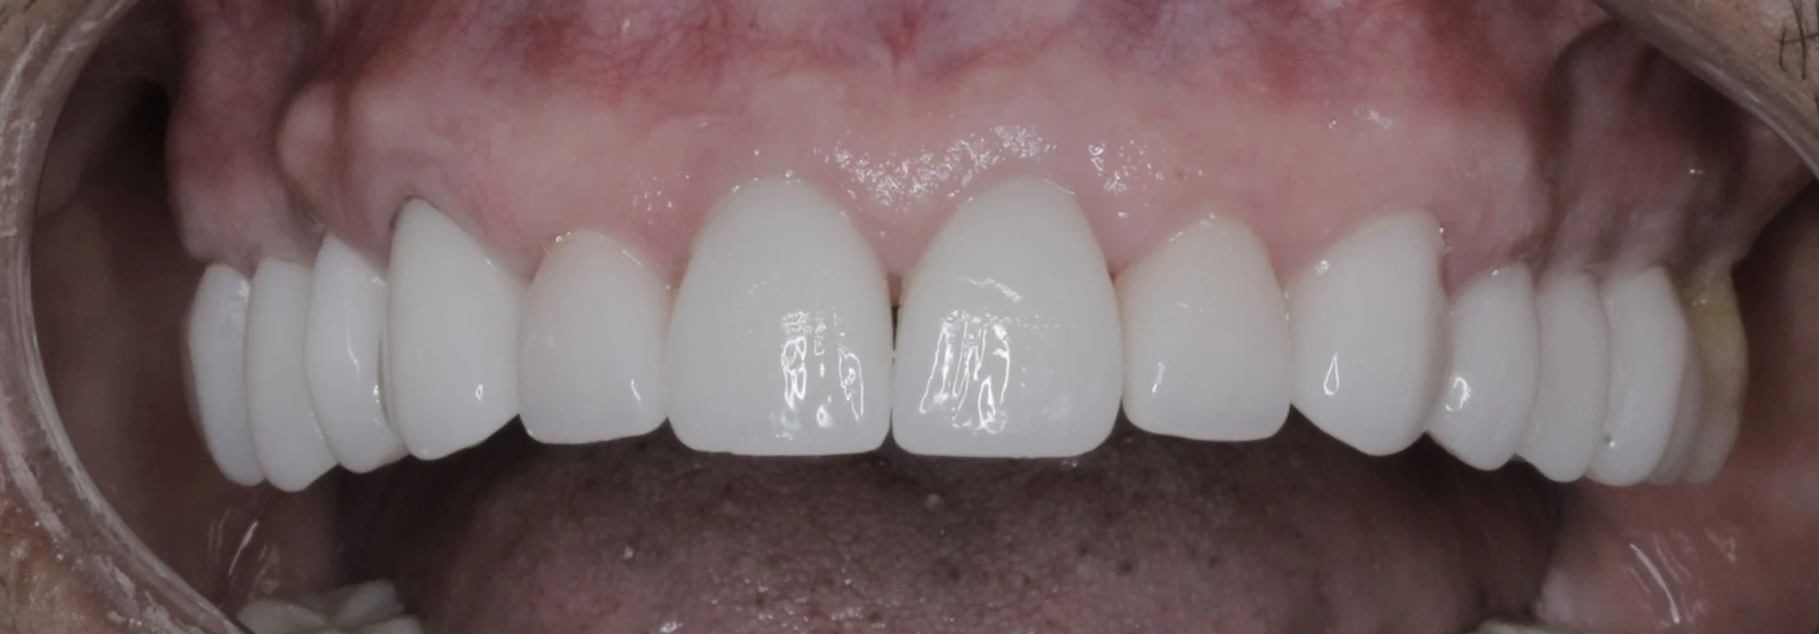

Fotografias finales

Después

Reemplazo de puente fijo + coronas

Nuevas coronas y carillas libres de metal de todos los dientes superiores.

Resultado final